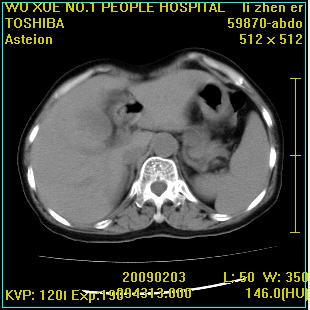

标题: CT18564:女,57岁,无不适,体验B超提示肾积水等 [打印本页]

标题: CT18564:女,57岁,无不适,体验B超提示肾积水等

左肾及左输尿管上端结石,左肾重度积水并左肾萎缩(不排除左肾先天性发育不良)。

左输尿管上端结石,左发育不良性多囊肾并积水;

右肾代偿性增大并肾盂积水,脾大。

左肾及左输尿管上端结石,基本上丧失肾功能了。

此患都左肾呈囊性变,边缘有高密度钙化,还是考虑结核吧.